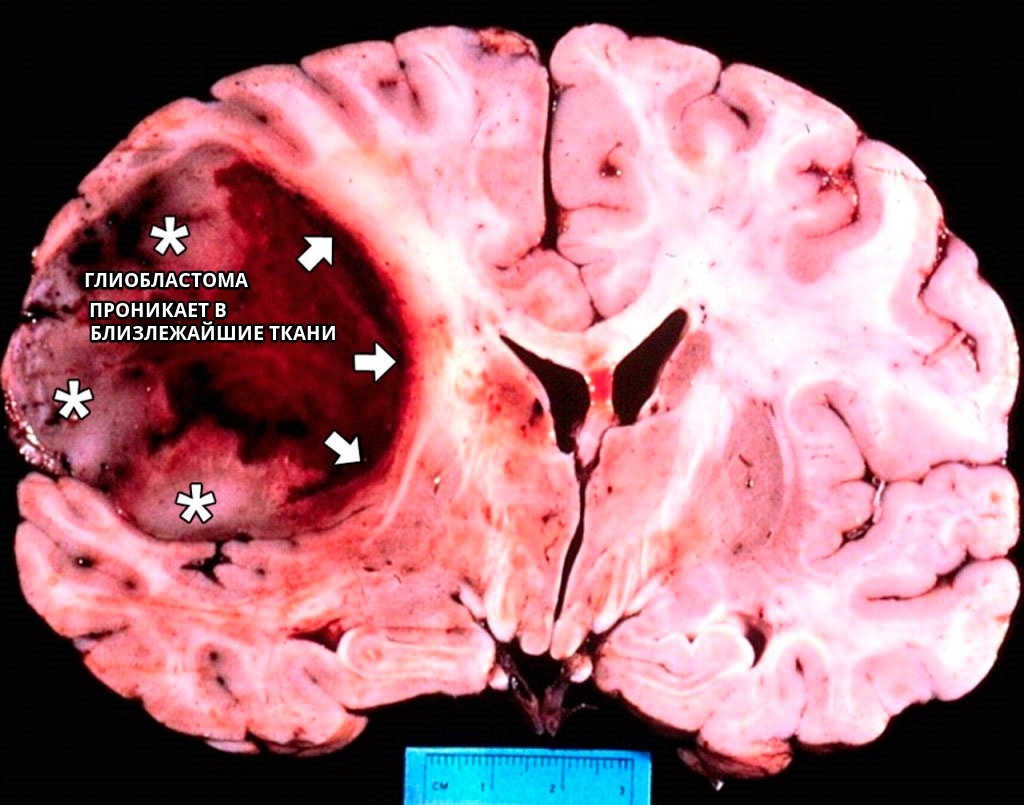

Для глиобластом характерно безладне скупчення клітин пухлини з збільшеною кількістю ядер, які перемежовуються з вогнищами некрозу і змінених судин.

Даний вид злоякісного утворення, що з’являється в головному мозку, дуже небезпечний через швидкого зростання та відсутність чітких розмежувань між ураженими і здоровими тканинами.